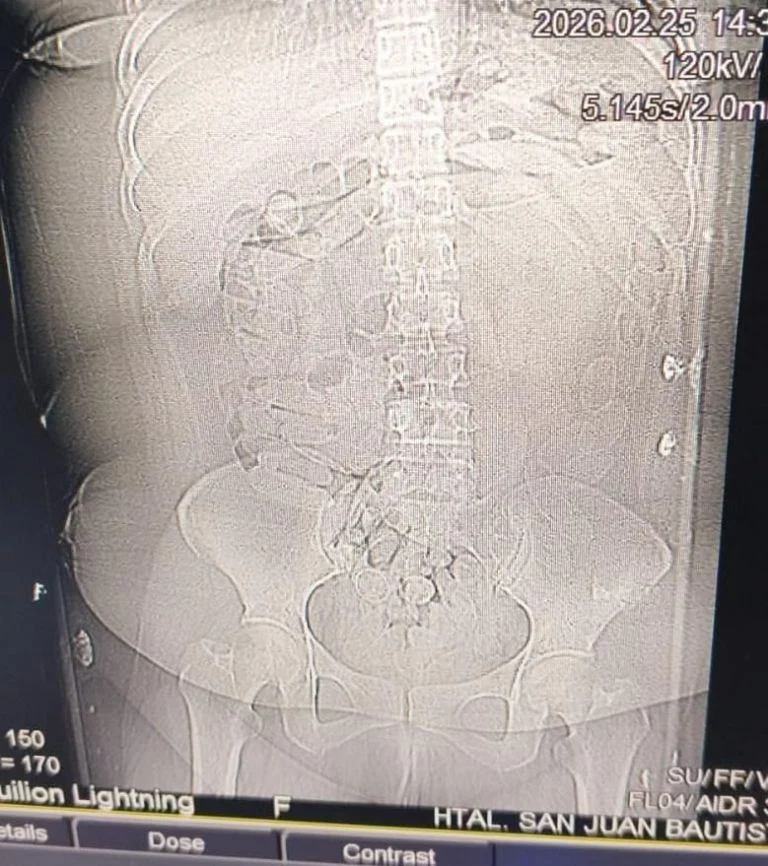

Durante el traslado, la mujer sufrió convulsiones y debió ser asistida de urgencia en el Hospital San Juan Bautista. Tras los estudios médicos se confirmó la presencia de los cuerpos extraños, y los 90 envoltorios contenían cocaína, según la prueba de campo Narcotest.